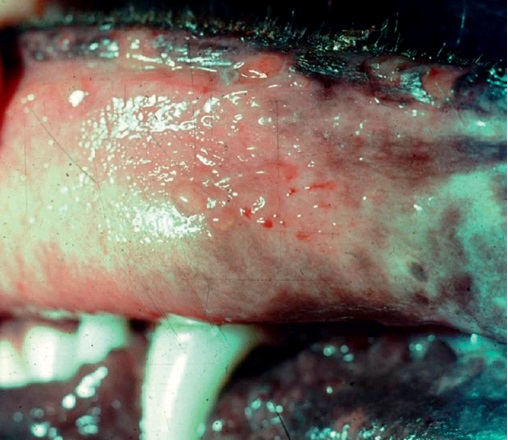

Фото 6. Буллезный пемфигоид у собак и кошек. Неповрежденные везикулы на слизистой ротовой полости и язвы на краях губ.